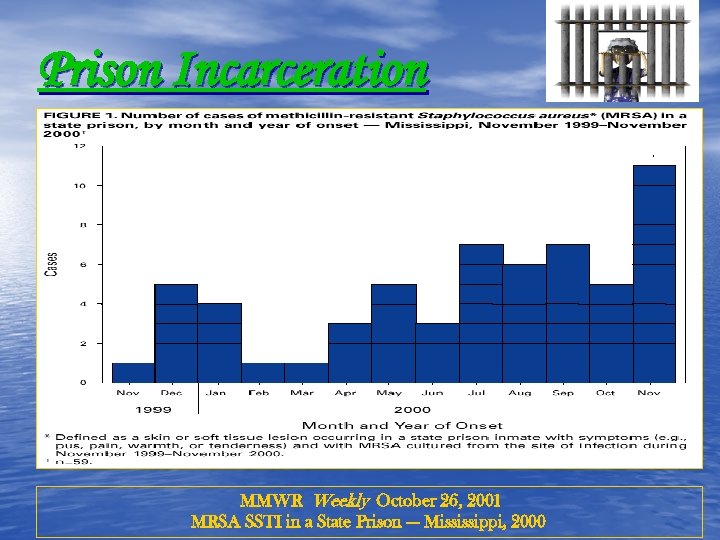

Prison Incarceration MMWR Weekly October 26, 2001 MRSA SSTI in a State Prison --- Mississippi, 2000

Prison Incarceration MMWR Weekly October 26, 2001 MRSA SSTI in a State Prison --- Mississippi, 2000